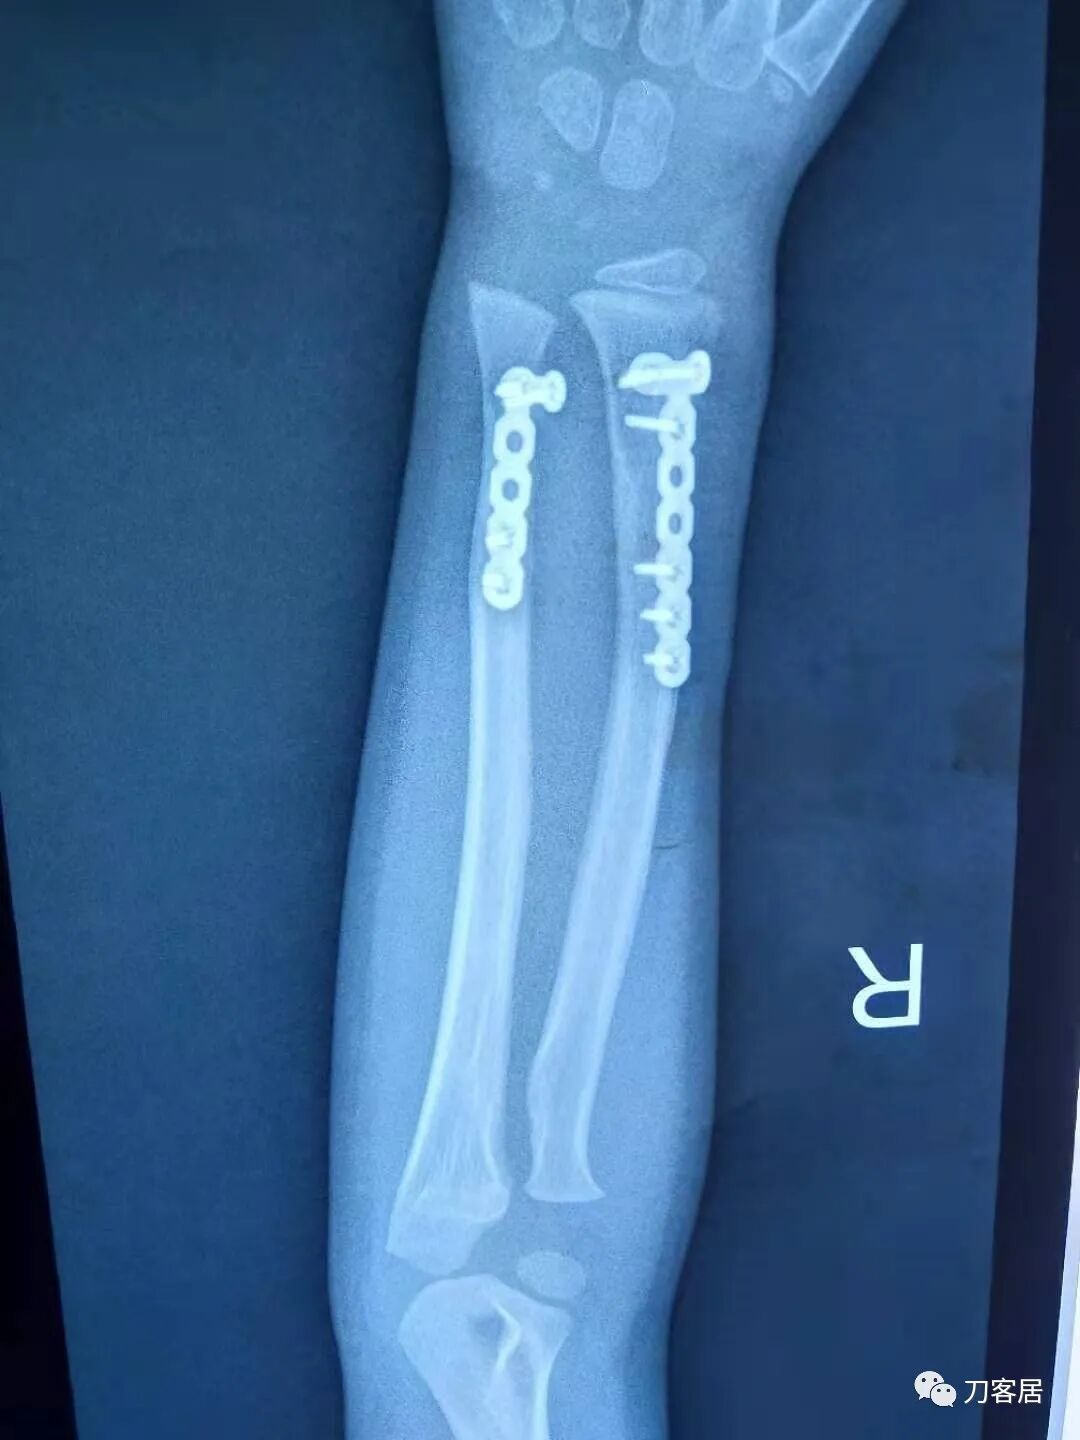

下面是这个6岁孩子,尺桡骨远端双骨折的术前及术后片子和外观照片。

2.  这个骨折处理起来也很简单,单纯的打石膏托或者中医的小夹板,或者正规的包括腕关节和肘关节的管型石膏外固定4周即可治愈该骨折。实在不行,如果这个孩子比较听话,不太调皮的话,用一本书,一个三角巾悬吊固定4周,都可以治愈该骨折。但是给这个患者用外固定架做了手术,而且桡骨远端的几颗克氏针距离骨折线太近,其中一枚克氏针进入到骨折间隙内。从这个术中图片来看,术者的外固定手术技术也有待于进一步的提高。毕竟术者应该还很年轻。从X线片来看,前臂及手的尺侧有不透光影,应该还使用了外固定石膏绷带托,而且我猜测应该是高分子的石膏绷带托,这个是纯属猜测,不一定是对的,不过如何解释前臂尺侧的不透光影呢?如果真是用了石膏绷带外固定的话,那为啥要做手术呢?外固定架术后就不该再用石膏绷带托辅助了。